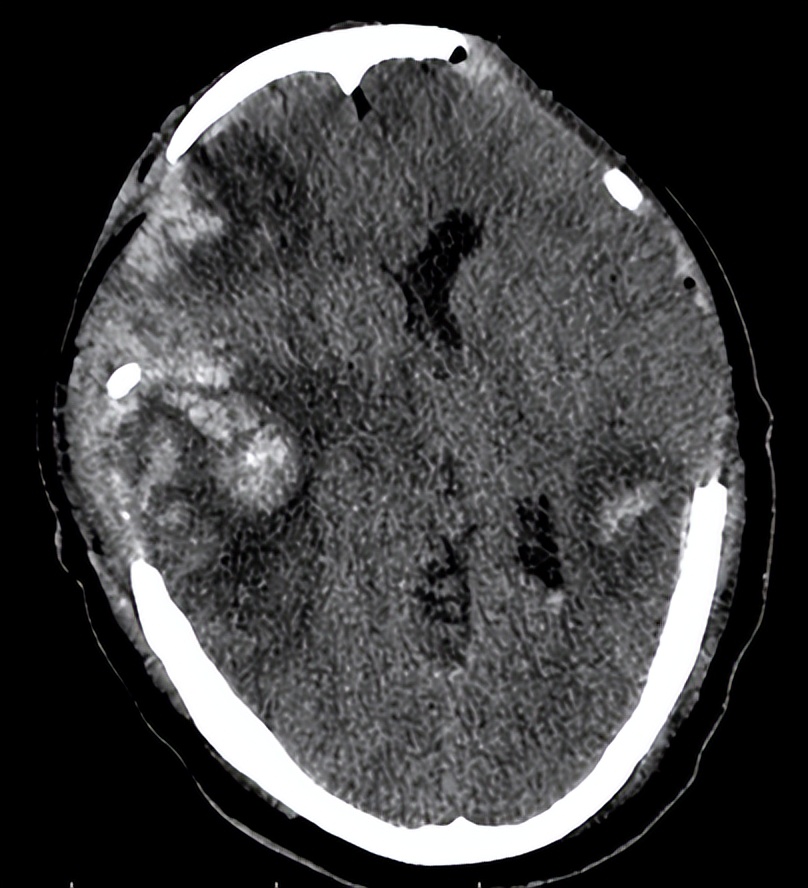

术后第三天,复查头颅CT(见下图)提示患者 脑水肿较前明显, 中线较前移位明显。目前正处在脑水肿高峰期,如果中线移位继续加重时,有必要 再次开颅 进行血肿清除。 病情危重 ,院方向患者家属交待病情,家属中有一位懂医的,都表示理解。

06-10(术后第三天复查头CT)

我被邀请查看了该患者。我先看了6月10日的头颅CT,又亲自检查了患者。

当时患者仍呈 昏迷状态 ,血压148/70mmHg,自主呼吸不规则,需有创呼吸机辅助通气,痰多,有明显痰鸣音。双侧瞳孔等大,约1.5mm,对光反射消失。脑干反射明显减弱。疼痛刺激右下肢回缩反应,左下肢无肢体回缩,双侧巴氏征阳性。

最近一次头颅CT,脑水肿明显,中线移位,双侧脑组织有继发性血肿。